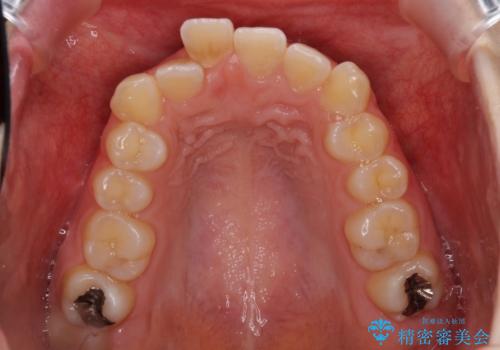

- 口の閉じにくさと割れてしまった奥歯を気にして来院された患者様です。

IPR(歯と歯の間を削る)と歯列全体の後方移動によって口元が引っ込むように設計し、インビザラインにより治療を行うこととしました。

割れてしまった奥歯は抜歯し、矯正治療中の良いタイミングでインプラントを埋入することとしました。

上下正中がずれていたため、抜歯による矯正治療も検討しましたが、口元がそれほど突出していなかったため、非抜歯にて矯正することになりました。

その結果正中のズレは残りましたが、口を閉じたときの感覚や奥歯の咬み合わせには全く問題なく、患者様には大変満足していただきました。